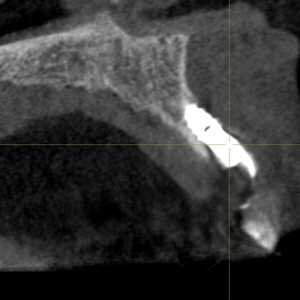

Dans cet article, nous présentons un cas clinique qui montre comment une mauvaise mise en place d'un implant peut rendre impossible la réhabilitation prothétique, ce qui nécessite une nouvelle planification chirurgicale et de réhabilitation pour obtenir l'esthétique souhaitée. Le patient se présente à notre observation avec une réhabilitation prothétique incongrue, avec bride en résine, support dentaire et implantaire, avec la présence d'un implant en position 2.1 vestibulaire et avec l'émergence dans le fornix, dans la mucosa alvéolaire. L'évaluation de la tomodensitométrie montre la position incorrecte de l'implant et la perte constante dans le sens transversal de la structure osseuse (Figs. 1, 2). Par conséquent, le plan de traitement suivant a été choisi : retrait de l'implant et préparation prothétique de l'élément 2.3, fabrication d'un premier support dentaire temporaire pour guider la cicatrisation des tissus (Figs. 3-7). Après 4 mois, une greffe d'épithélium conjonctif libre est réalisée avec ablation du palais pour compenser l'espace transversal des tissus mous, puis le provisoire est remodelé afin de faciliter la cicatrisation des tissus (Figures 8-11). Après 9 mois de maturation des tissus, la finalisation prothétique fixe avec support dentaire est réalisée (Figs. 12-14).